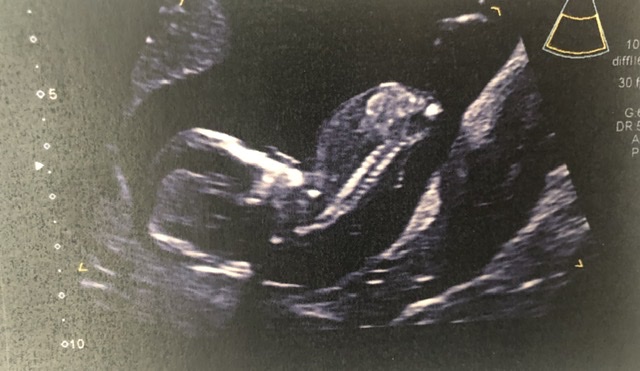

Just wondering if anyone had any guesses on these 13wk ultrasounds for fun?

I’m assuming that’s not a penis on the leg shot any maybe the cord but I can’t work out anything and I don’t think the nub is visible in the other pic Attachment 42785

Unfortunately these are not suitable for guessing. The top pic has the back of the baby's head (you can see the little ear there) and on the bottom pic,, 13 weeks is too early for potty shots. Boys and girls look the same from beneath at that stage of gestation.

No nub seen but looks similar to my 13 week scan between the legs when I had a girl so guessing girl. Take my guess with a pinch of salt though as it is a bit too early. Hope you get whatever your preference is if you have one